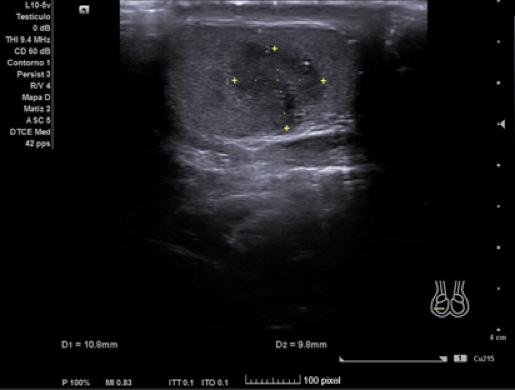

Hallazgos ecográficos

Ecografía Clinica: testículo izquierdo de tamaño y ecogenicidad normales, con microcalcificaciones y colas de cometa. Testículo derecho más pequeño que el contralateral, y en su zona central una lesión hipoecoica lobulada e irregular con captación intralesional y calcificaciones puntiformes en parénquima testicular. Con la sospecha de una neoplasia del testículo derecho se consulta con Urología, que solicita analítica y cita.

Los marcadores tumorales (LDH, BHCG, alfafetoproteína) son negativos y la ecografía se repite de forma reglada para descarte de neoplasia testicular. En esta última se define un teste derecho disminuido de tamaño y ecoestructura heterogénea, con áreas centrales hipoecogénicas aunque sin lesiones claramente definidas.

El diagnóstico de sospecha tras ser evaluado por Urología es una atrofia testicular derecha. En el diagnóstico diferencial se debe incluir la posibilidad de que la atrofia sea por una torsión testicular previa, una orquitis u orquiepididimitis que cause atrofia secundaria, traumatismos, infartos testiculares no traumáticos y neoplasia testicular. La ecografía clínica tiene parte de concordancia con la reglada, sin embargo, en esta última no se define la lesión hipoecoica lobulada e irregular que nos hace sospechar en AP que pueda tratarse de una lesión tumoral.